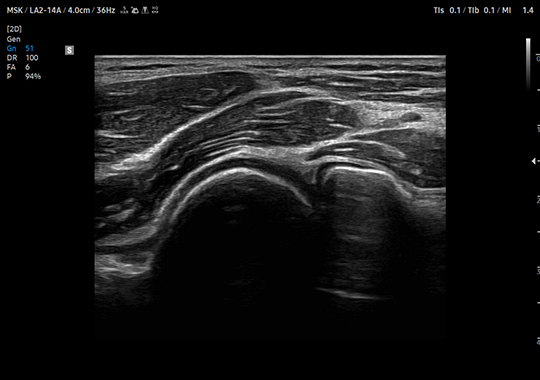

LA2-14A

- Wide Band Linear

- Application: Abdomen, Musculoskeletal, Pediatric, Small Parts, Thoracic, Vascular